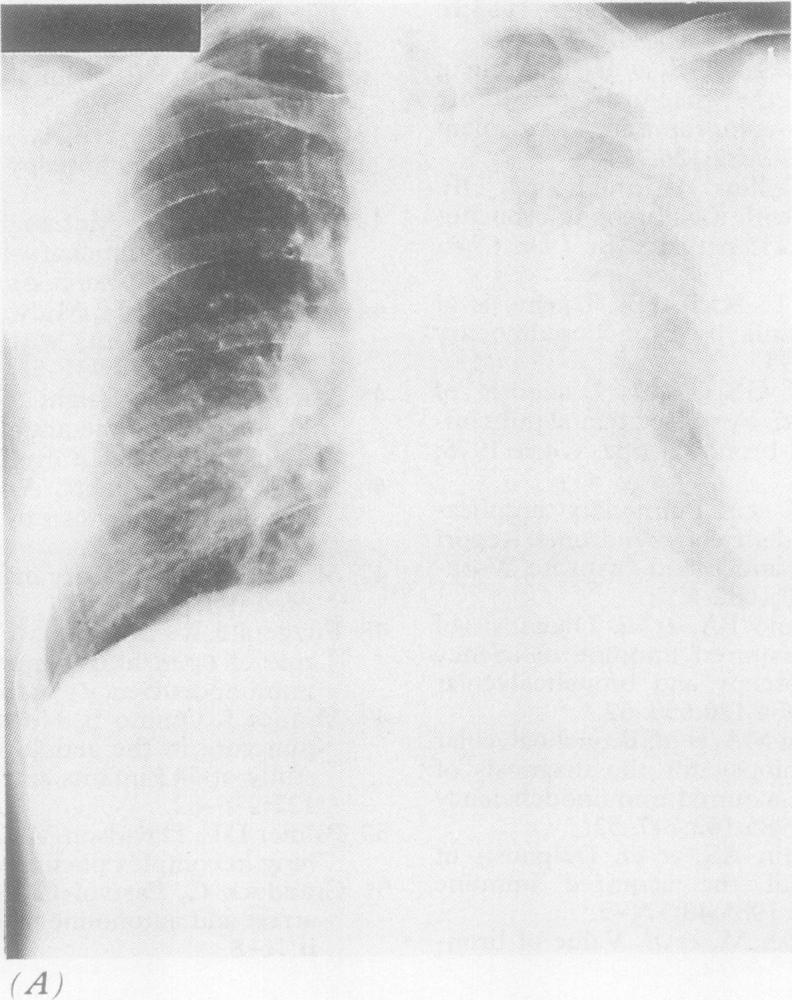

A patient is described who presented with left upper lobe collapse due to endobronchial metastatic prostate carcinoma. Treatment with the oral antiandrogen cyproterone acetate resulted in resolution of the occluding endobronchial carcinoma and lobar re-expansion.

报告了1例因支气管内转移性前列腺癌导致左上叶肺不张的患者。口服抗雄激素药物醋酸环丙孕酮治疗后,阻塞性支气管癌消退,肺叶复张。